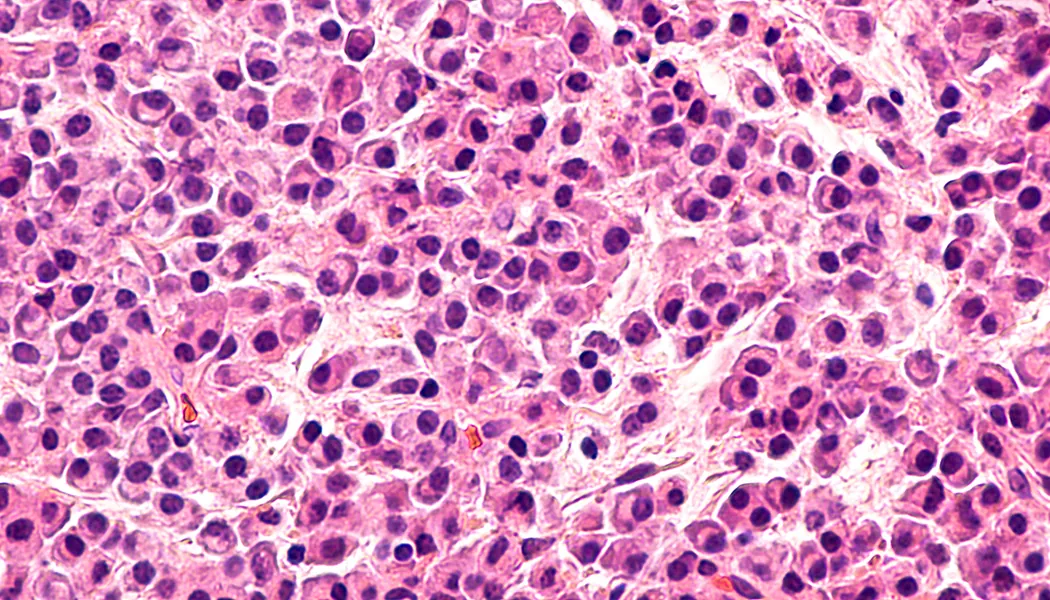

Multiple myeloma (MM) is a bone marrow cancer that affects plasma cells. Bone marrow is the soft and spongy tissue which resides in the cavities of many of our bones. It is rich in cells which produce new blood cells. On average, 500 billion new blood cells are produced each day within the bone marrow. These cells can be categorized as either lymphoid (producing lymph cells) or myeloid (producing red blood cells, white blood cells (including plasma cells) and plasma). Normally, plasma cells work as part of the immune system to produce antibodies which can recognize and neutralize pathogens; but in MM, these cells become cancerous and grow out of control, leading to multiple painful bone tumors, as well as anemia, kidney failure and recurrent infections. MM relapse rates are quite high because of the inherent challenge of immunosuppression, given that the immune system itself is directly compromised. As a result, immunology has been a major focus of new treatment methods.